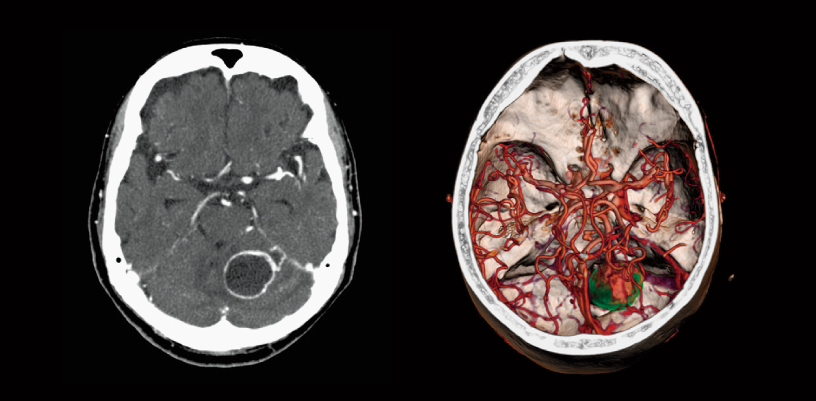

Brain tumor